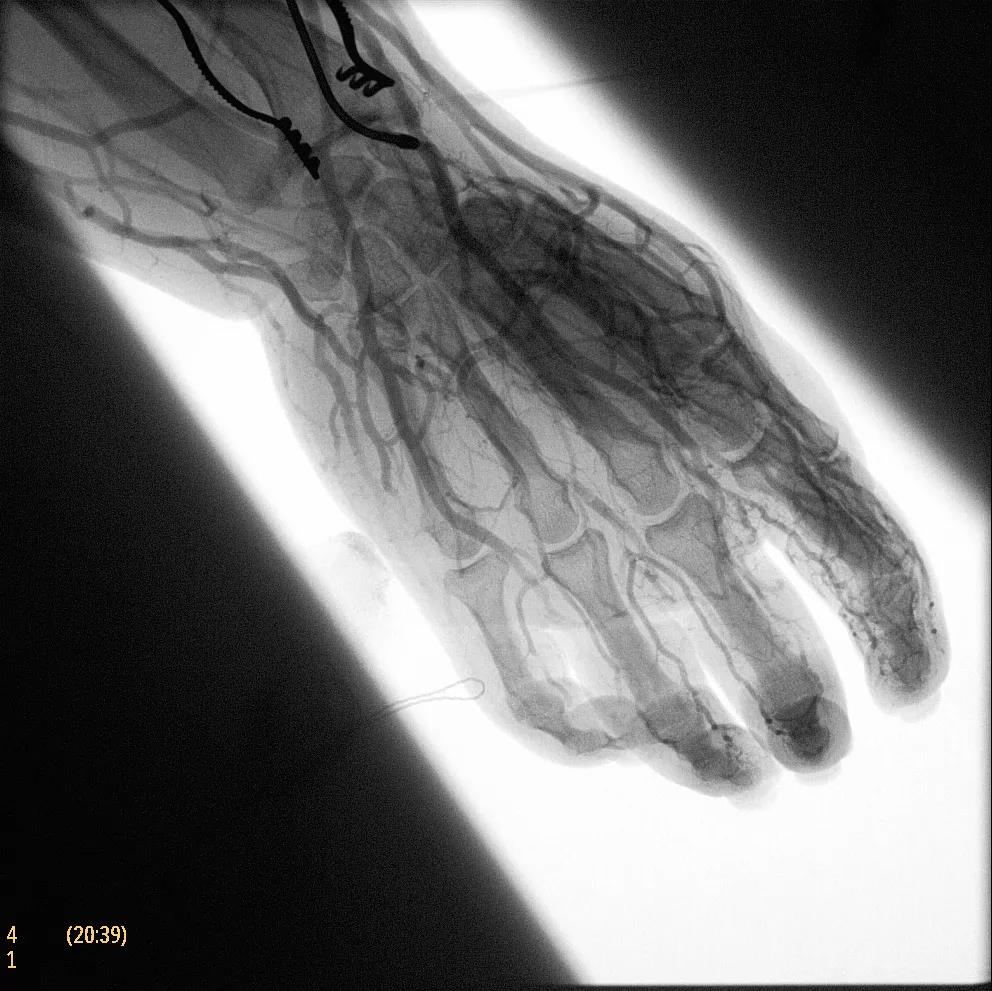

飛利浦于2019年2月18日宣布推出帶扁平探測器的移動式C臂Zenition 70。Zenition 70使用飛利浦第四代Flat Detector系統(tǒng),具有卓越的成像清晰度和靈活性,可執(zhí)行各種情況。

據(jù)器械之家了解到,移動式C型臂是X射線系統(tǒng),可帶入手術室(OR),在整形外科、創(chuàng)傷和血管手術等各種手術過程中提供實時圖像引導。Zenition70使醫(yī)院能夠最大限度地提高OR性能,增強臨床能力并為員工提供高質(zhì)量的用戶體驗。

( Zenition 70匯集了圖像捕獲,圖像處理,易用性和多功能性方面的創(chuàng)新。)

在快速增長的圖像引導微創(chuàng)手術領域 ,手術干預的范圍和復雜性在繼續(xù)增加,需要治療的患者數(shù)量也在增加。為了以更低的成本治療更多的患者,醫(yī)院需要具有不同能力的多功能C臂組,以便容易地適應不同類型的手術和不同操作者的需要。Zenition 70易于在手術室之間移動,易于在患者周圍定位并且操作直觀。

飛利浦Zenition 70支持整個醫(yī)療保健機構提高OR性能。平臺類似平板電腦的用戶界面和簡單的統(tǒng)一工作流程意味著一旦操作員學會在平臺上使用一個系統(tǒng),他們就可以輕松地操作它們。該系統(tǒng)可在任何介入或外科手術過程中快速直觀地拍攝傻瓜相機。Zenition的緊湊設計,位置記憶功能(僅適用于Zenition 70)和BodySmart軟件,即使在圖像增強器或平板探測器的邊緣也能捕捉快速一致的圖像,將C臂重新定位的需求減少45%。

( Zenition 70采用與Azurion平臺相同的圖像處理算法。

為了獲得清晰的高質(zhì)量圖像,Zenition 70 采用了與公司Azurion平臺相同的圖像處理算法,可提供患者解剖結構的高清可視化和更大的可視區(qū)域。飛利浦的MetalSmart軟件等功能可確保圖像質(zhì)量,該軟件可自動調(diào)整圖像的對比度和亮度,以便在視野中存在金屬物體(如植入物)時提高圖像質(zhì)量 - 這一特性使Zenition 70在整形外科中特別有用。